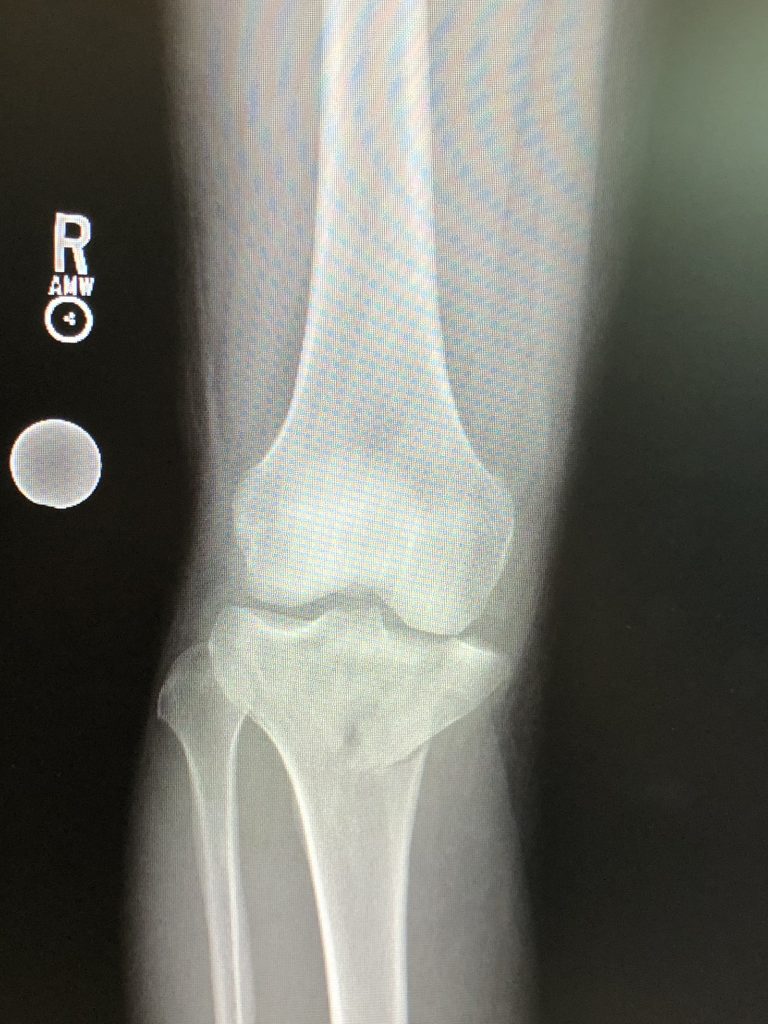

On January 4, 2023, I was injured in a freak golf cart accident while on vacation in the Florida Keys. The golf cart I was driving rolled over and pinned my leg. I was instantly struck with excruciating pain and I was rushed by ambulance to an area hospital where I was found to have suffered a severe tibial plateau fracture along with a torn meniscus and MCL and cartilage injury. The orthopedic surgeon in Florida recommended I go to New York for treatment as it was an extremely severe injury that required expert care.

The surgery was extremely complex and took nearly 9 hours start to finish but Dr. Dvorzhinskiy, with the help of resident Dr. Gregory Kazarian, successfully rebuilt my shattered leg. My post-operative x-rays are a testament to his incredible talent as a surgeon and the way in which he reconstructed the shattered tibia and salvaged the detached cartilage enabled me to recover to the point where less than 9 months after the surgery I can walk and even exercise with minimal pain and have a long active and healthy life to look forward to.